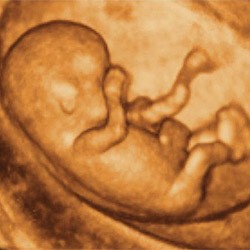

A USG 4D to takie gdzie dziecko widać nie prześwietlone gdzie widać kości i wszystkie wnętrzności a w trójwymiarze (Jak na zdj) w ruchu. Czyli rozpoznanie wad genetycznych jest raczej niemożliwe.

• usg4d.jpg

usg4d.jpg

14,8 KB · Wyświetleń: 102